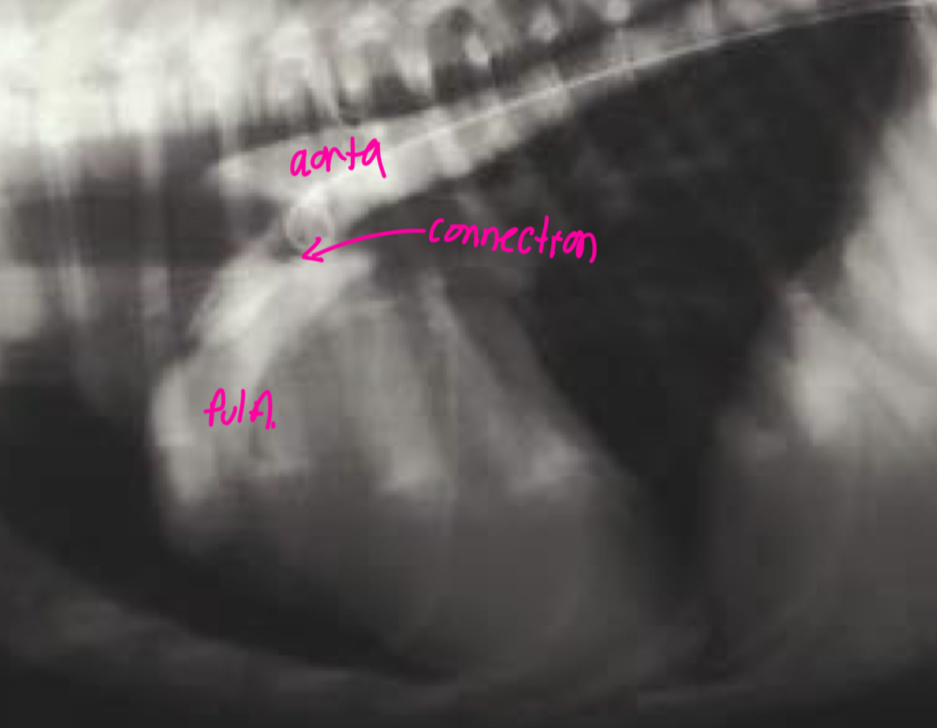

What does the angiocardiography highlight in aortic stenosis

-AA bulge

-increased cardiac waist

-left ventricular hypertrophy

-narrowing of aortic outflow tract

-post stenotic dilation of AA

± mitral regurg

What disease does this dog have

Aortic stenosis